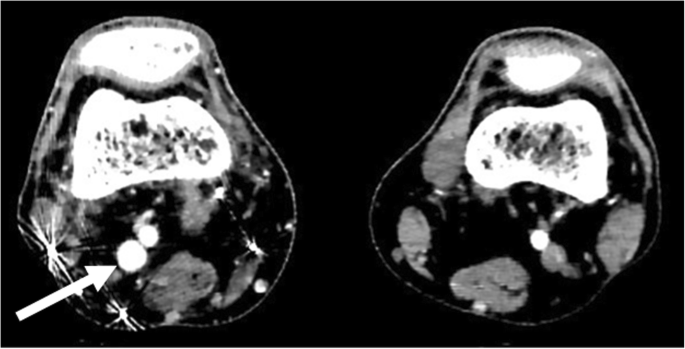

Arterial duplex scan showed high diastolic flow in the PTA and an arterialized flow in the posterior tibial vein (PTV). A reversed flow in the distal PTA was also noted. Indeed, a communication was eventually found at the level of mid-to-distal leg between PTA and PTV (Fig. 1). Computed tomographic angiography (CTA) showed early filling of the right popliteal and superficial femoral veins (SFVs), as well as dilated superficial veins of RLE, but could not identify the location of the AVF due to multiple pellets artifacts (Fig. 2). However, the brisk and substantial filling of the femoral vein on the arterial phase raised the possibility of a more proximal fistula than the distal leg. Angiography was planned with intension to treat depending on findings.